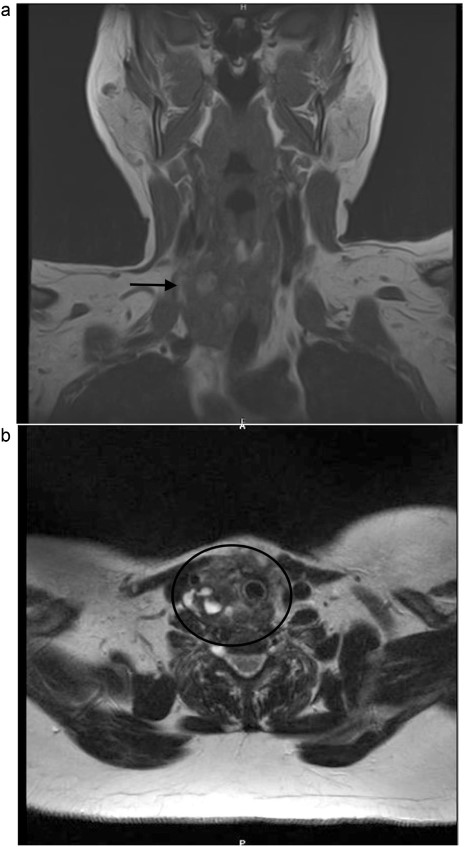

A 53-year-old Caucasian German woman with a medical history of hypertension and depression presented with a rapidly growing neck swelling on the right side, accompanied by a degree of induration. She had undergone right hemithyroidectomy 27 years ago for nodular goiter, resulting in right-sided recurrent laryngeal nerve palsy. However, 15 years prior to her presentation at our hospital, she underwent a left-sided hemithyroidectomy without complications. All thyroid function tests showed results within the normal ranges. Magnetic resonance imaging revealed a suspicious mass measuring 3 × 3.2 × 4.8 cm on the right side of the thyroid gland (Fig. 1). Concerns regarding the possibility of thyroid remnant and potentials for thyroid malignancy have been raised. The patient underwent surgical excision of the inflamed tumor from the neck musculature. The tumor was successfully extracted along with a staggering 20 thick ligation sutures, and the mini-abscesses were also managed (Fig. 2). During surgery, a tiny, benign thyroid remnant was found. Histological examination revealed a chronic fibrosing suture granuloma, with some areas showing focal active inflammation and foreign body reaction. Postoperative follow-ups showed marked improvement in the patient’s symptoms, without tumor recurrence.

(a, b) Neck MRI, showing a mass 3 × 3.2 × 4.8 cm at the right thyroidectomy bed.